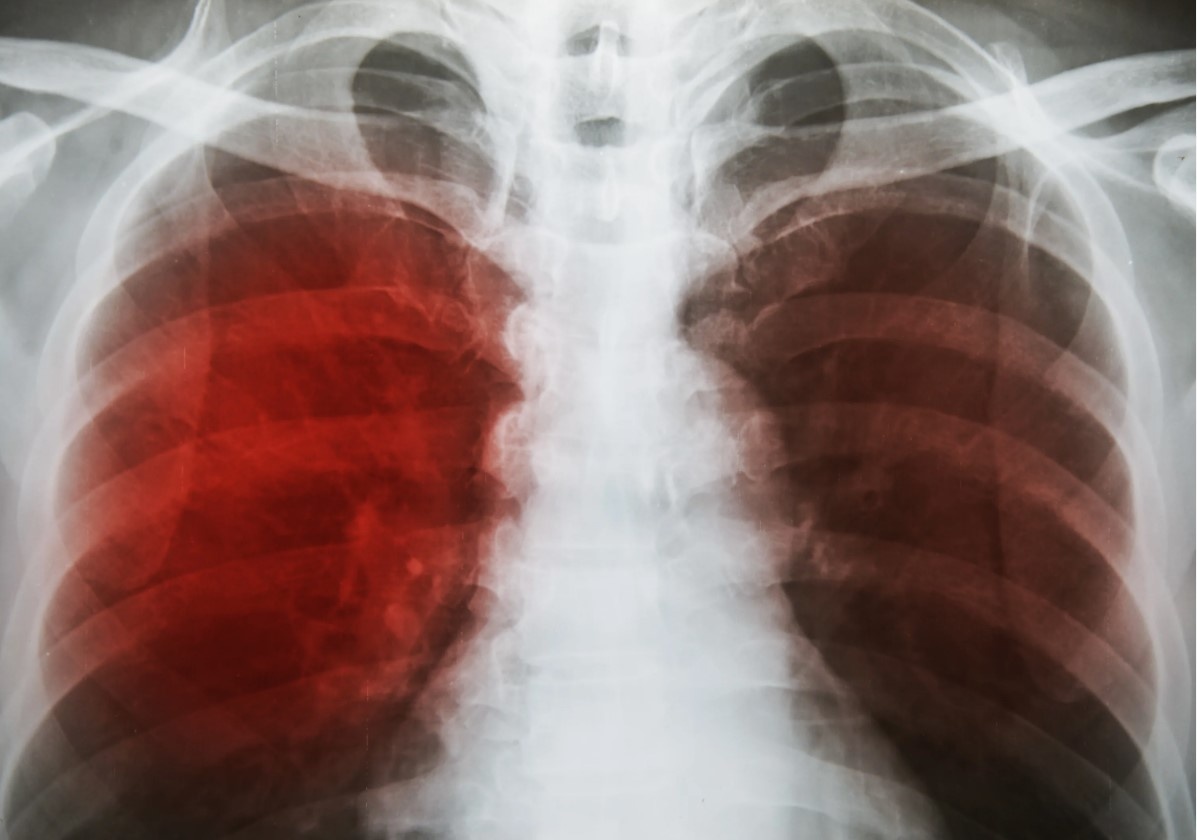

Кашель с кровью, или гемоптизис, — тревожный симптом, который встречается у 5–15% людей с респираторными проблемами и часто ассоциируется с туберкулёзом, заболеванием, поражающим 10 миллионов человек ежегодно, по данным Всемирной организации здравоохранения (ВОЗ). Однако этот симптом может быть признаком более опасных состояний, таких как рак лёгких (2,2 миллиона случаев в год), лёгочная эмболия или бронхоэктатическая болезнь, особенно у людей старше 50 лет, когда риск серьёзных патологий возрастает на 15% каждые 10 лет. Игнорирование кашля с кровью может привести к поздней диагностике, снижая выживаемость до 20–30% при раке лёгких или лёгочной эмболии. В этой статье мы подробно разберём, почему кашель с кровью не всегда связан с туберкулёзом, какие состояния могут быть хуже, их механизмы, симптомы, диагностику и профилактику. Ключевые слова: кашель с кровью, гемоптизис, туберкулёз, рак лёгких, лёгочная эмболия, бронхоэктазы, пневмония, диагностика, профилактика, здоровье лёгких. Гемоп

Кашель с кровью, или гемоптизис, — тревожный симптом, который встречается у 5–15% людей с респираторными проблемами и часто ассоциируется с туберкулёзом, заболеванием, поражающим 10 миллионов человек ежегодно, по данным Всемирной организации здравоохранения (ВОЗ). Однако этот симптом может быть признаком более опасных состояний, таких как рак лёгких (2,2 миллиона случаев в год), лёгочная эмболия или бронхоэктатическая болезнь, особенно у людей старше 50 лет, когда риск серьёзных патологий возрастает на 15% каждые 10 лет. Игнорирование кашля с кровью может привести к поздней диагностике, снижая выживаемость до 20–30% при раке лёгких или лёгочной эмболии. В этой статье мы подробно разберём, почему кашель с кровью не всегда связан с туберкулёзом, какие состояния могут быть хуже, их механизмы, симптомы, диагностику и профилактику. Ключевые слова: кашель с кровью, гемоптизис, туберкулёз, рак лёгких, лёгочная эмболия, бронхоэктазы, пневмония, диагностика, профилактика, здоровье лёгких.